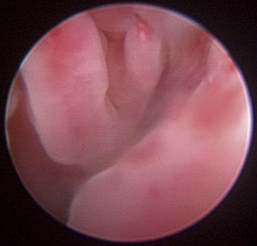

The hallmark symptom of nasopharyngeal disease is stertor. Discharge, sneezing, reverse sneezing, and hacking may be present variably. If the main complaint is noisy breathing and not productive sneezing with nasal discharge, the nasopharynx may be the site of primary disease. The most common primary problems in the nasopharynx in cats are inflammatory polyps and tumors.12,13 Cats with polyps are generally young and have a history of noisy breathing. Sneezing and mucopurulent nasal discharge may be present, but the chief complaint is stertor and increased respiratory effort. This is a problem that often requires otoscopic as well as rhinoscopic intervention. With the patient placed in dorsal recumbency, the soft palate is reflected rostrally with the use of a spay hook, and the polyp is removed via traction and avulsion (Figures 19-18 and 19-19). The eustachian tube orifices can generally be directly visualized and any remaining tissue removed, if present. Both ears should be carefully examined, and transtympanic bulla curettage should be performed to remove any middle ear proliferative tissue (see Chapter 20). In older cats with similar symptoms, a neoplasm in the nasopharynx is more likely, and rhinoscopy is often much more rewarding (Figure 19-20). Foreign bodies can become lodged in this area after vomiting or pharyngeal nasopharyngeal spasms induced by attempted swallowing of the foreign object. Nasal and nasopharyngeal stenosis after trauma, nasogastric reflux,14 and chronic rhinitis can occur in dogs and cats (Figures 19-21 through 19-23). Reflux can occur during general anesthesia and can be a helpful clue if postoperative symptoms arise and persist. Congenital choanal atresia and nasopharyngeal dysgenesis have also been reported in dogs.15,16 Nonspecific chronic inflammation of the nasopharynx causes a cobblestone appearance of the mucosa due to the formation of hyperplastic lymphoid follicles (Figures 19-24 and 19-25). Chronic inflammation may be the result of a lymphoplasmacytic rhinitis complex or sometimes may be secondary to otitis media and middle ear drainage of infected secretions via the eustachian tube. Otoscopy is recommended in any patient with nasopharyngitis of unknown origin. CT studies performed in a population of 45 cats with chronic sinonasal discharge revealed effusive bulla disease in 28% of symptomatic cats.17 Unfortunately, we are unable to differentiate primary and secondary pathology based on the concurrence of nasal and middle ear disease. Regardless of the knowledge of the primary cause, both inflammatory foci should be treated to achieve symptom relief.

image

Figure 19-20 Feline nasopharyngeal adenocarcinoma.